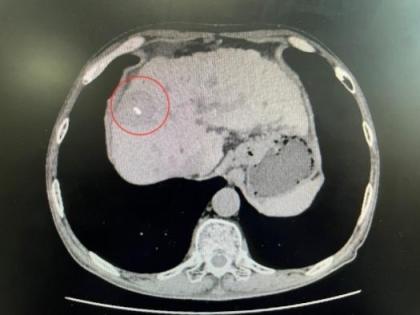

患者肿瘤紧贴膈肌

消融术中影像

患者消融术后2天复查病灶影像

消融术后2天复查显示,患者肿瘤已成功被灭活,膈肌功能正常,短时间内即可下床活动。据了解,“水隔离”辅助技术具备三大核心优势:一是安全性显著提升,将高风险手术转化为可控操作,杜绝严重并发症;二是实现肿瘤根治,打破“靠近关键脏器即消融禁区”的限制,治疗效果媲美外科手术切除;三是坚守微创理念,仅增加置管注冰水步骤,创伤小、恢复快。